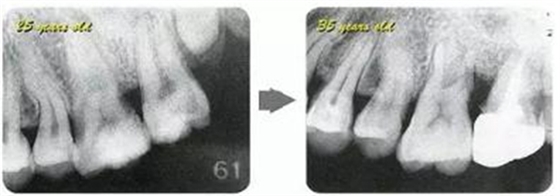

牙周病的發(fā)展因部位不同而發(fā)展程度不同的。10點(diǎn)后的狀態(tài)參考病例①和參考病例②的磨牙處的狀態(tài)相比較,思考下沒接受治療病情發(fā)展的特別性吧。

參考病例① 35歲女性

在左下第一磨牙在25歲時(shí)近中處可以看到垂直性的骨吸收,但35歲時(shí)吸收停止,原本沒有見到的遠(yuǎn)中處骨吸收的,現(xiàn)在卻吸收得很嚴(yán)重。

在右下處,原本有大量骨吸收的第一磨牙處的吸收卻變緩慢,原本沒有吸收的第二前磨牙卻出現(xiàn)了吸收。出現(xiàn)吸收的左上第一磨牙的遠(yuǎn)中處,吸收得越來越多了。

把10年間的變化做成表格。牙周病的發(fā)展根據(jù)各個(gè)人會(huì)不同,即使通一個(gè)人,不同牙齒,不同牙面發(fā)展的狀態(tài)也不同。